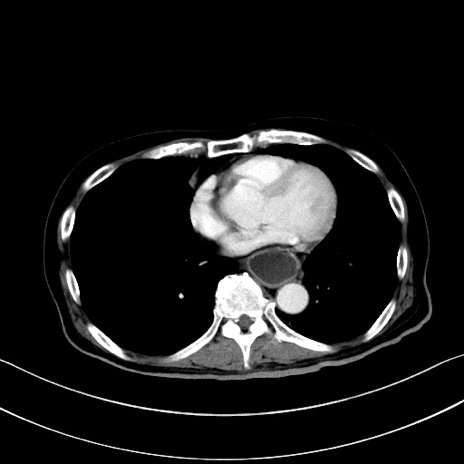

症例28(横断像)

【症例】60歳代男性

【主訴】嘔吐

【現病歴】胃癌にて胃全摘後。食思不振が悪化し、夜中に嘔吐することがある。

【既往歴】胃癌、胃全摘、脾摘、胆摘後

【データ】WBC 5900、CRP 10.56